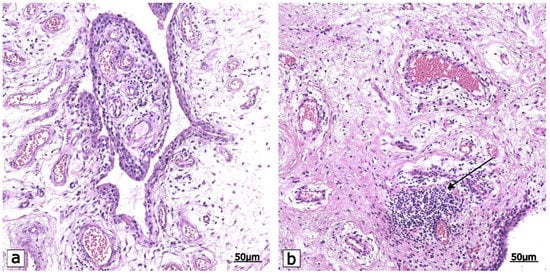

- Groma, V.; Tarasovs, M.; Skuja, S.; Semenistaja, S.; Nora-Krukle, Z.; Svirskis, S.; Murovska, M. Inflammatory Cytokine-Producing Cells and Inflammation Markers in the Synovium of Osteoarthritis Patients Evidenced in Human Herpesvirus 7 Infection. Int. J. Mol. Sci. 2020, 21, 6004. [Google Scholar] [CrossRef]